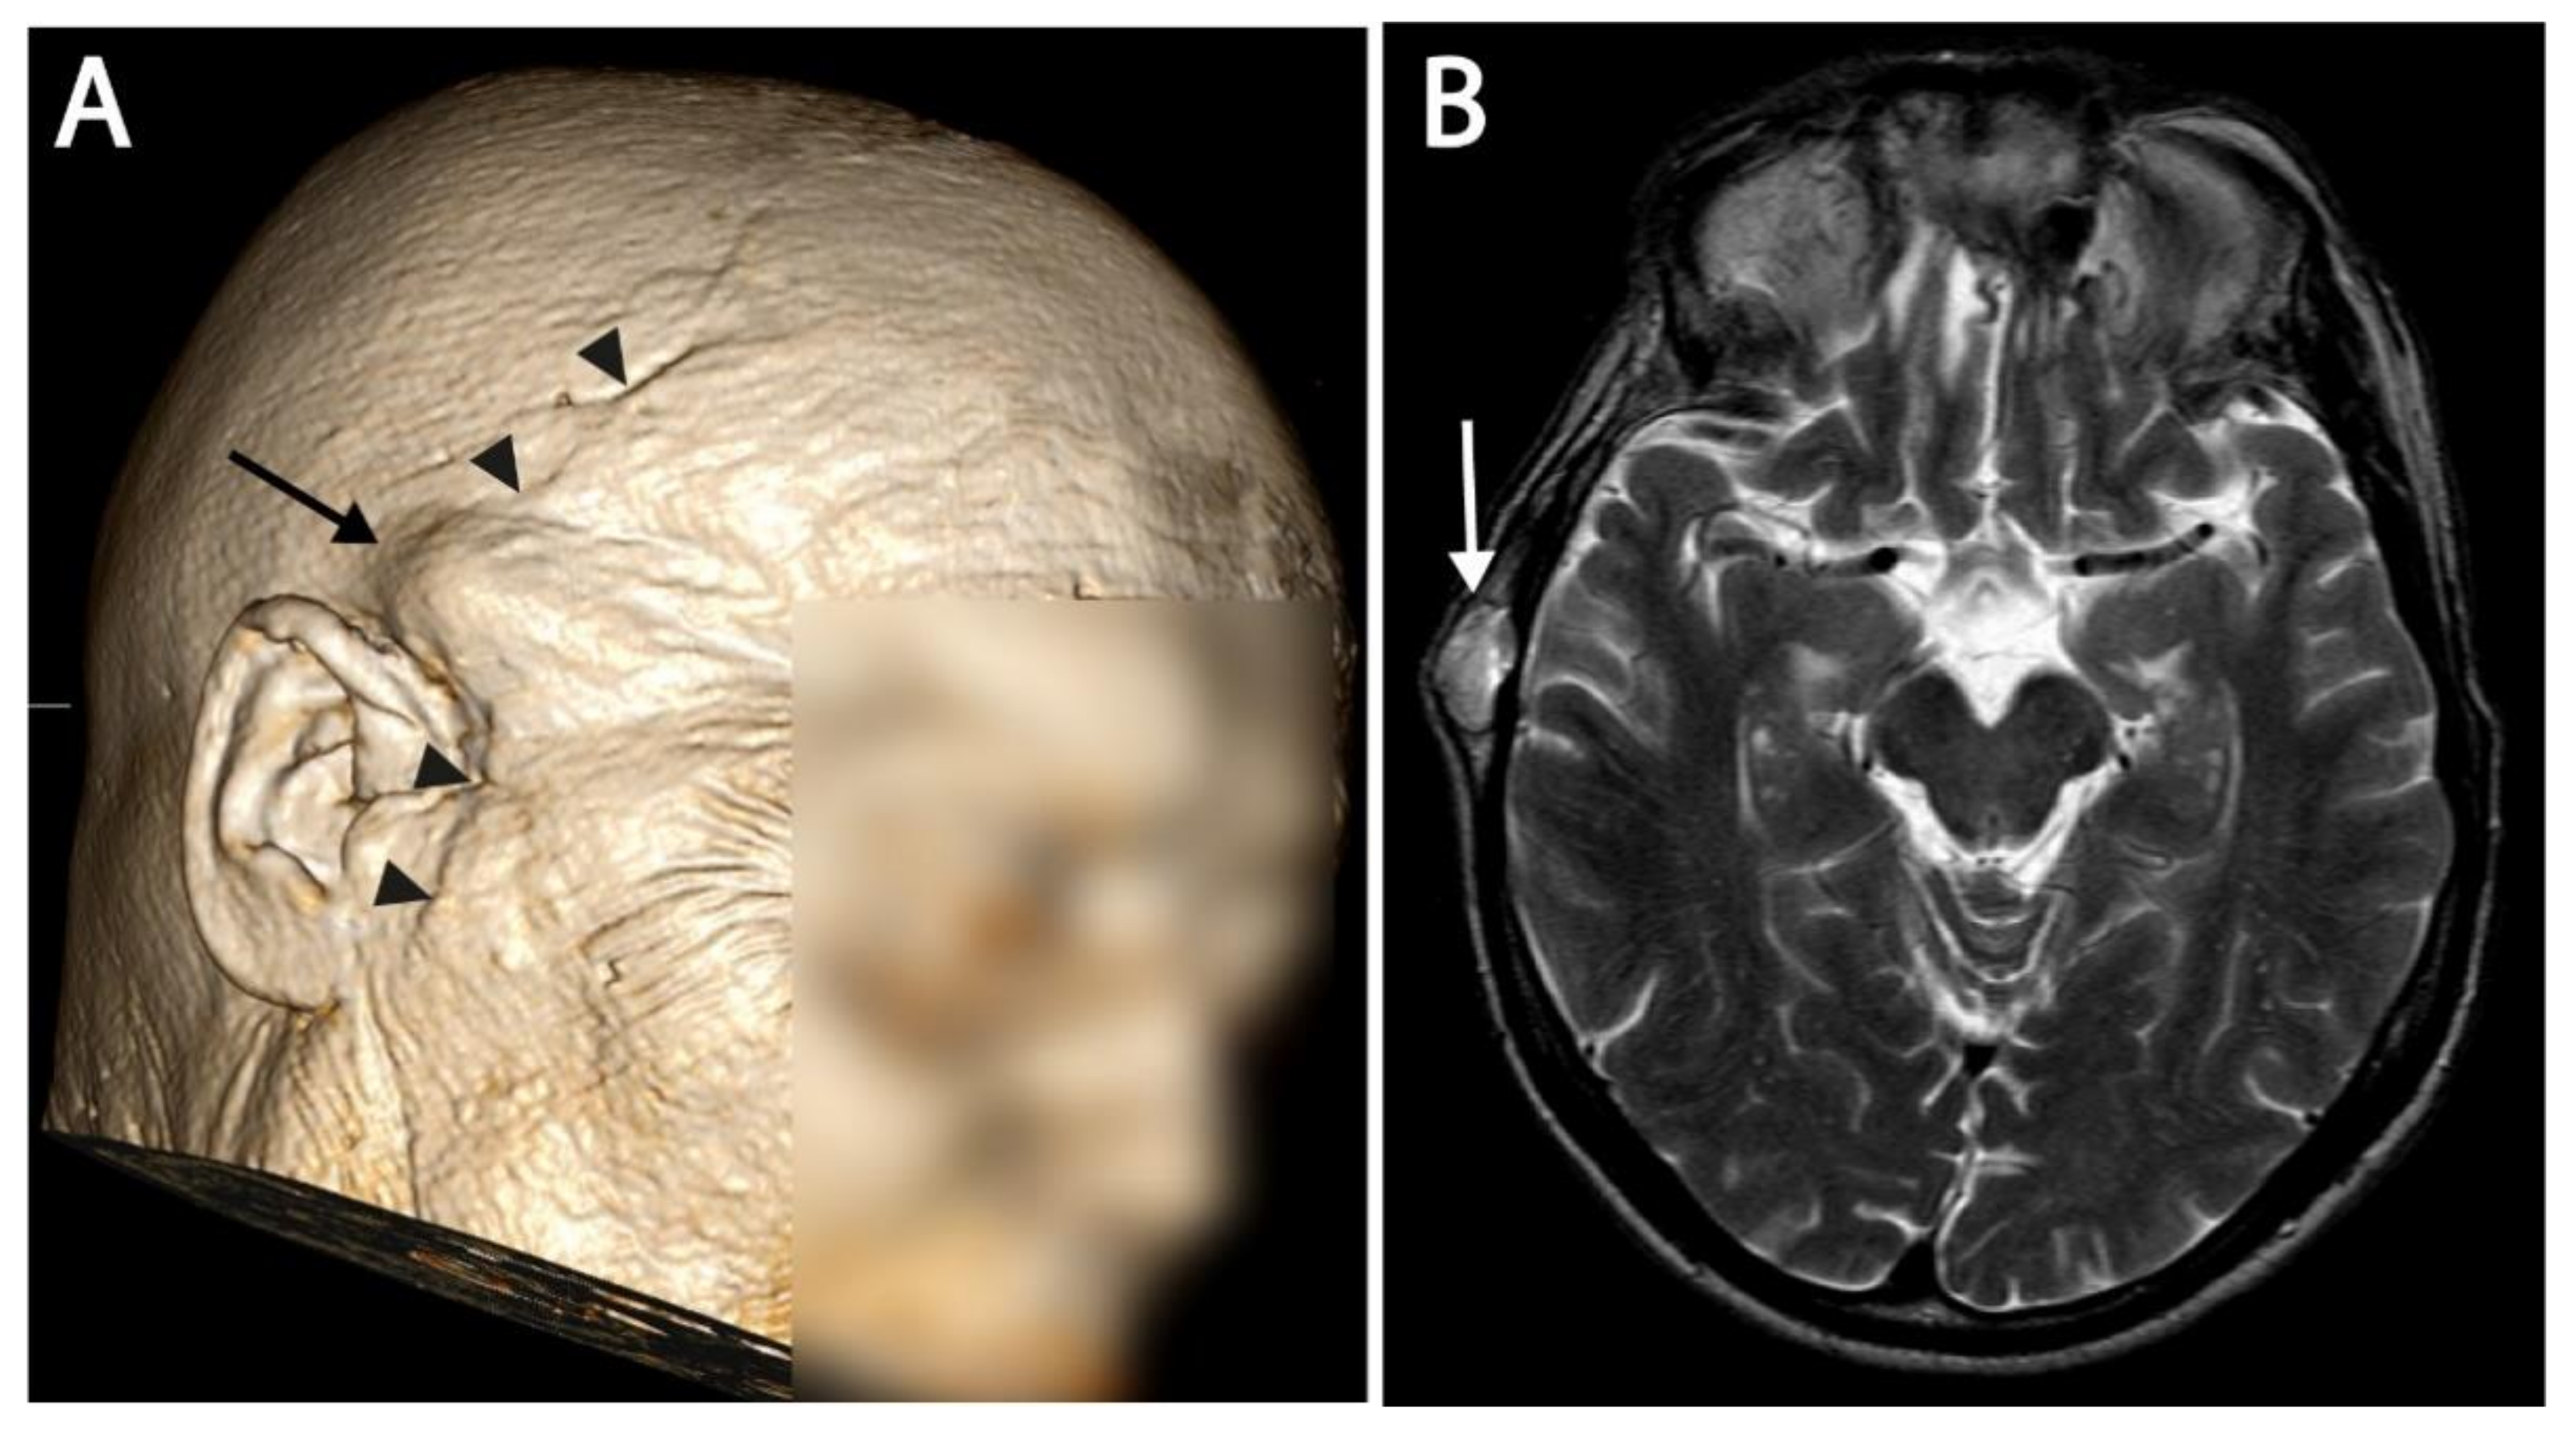

| 3 | Craniocervical junction |

| Proton | Subcutaneous retroauricular Subcutaneous neck 3x Neck muscle left + right | 18 | Surgery Photon radiotherapy (Linac) |